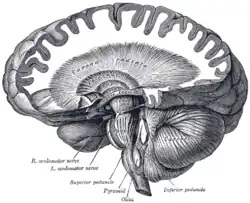

Dissection showing the course of the cerebrospinal fibers. | |

Superficial dissection of brain-stem. Lateral view.

Superficial dissection of brain-stem. Lateral view.